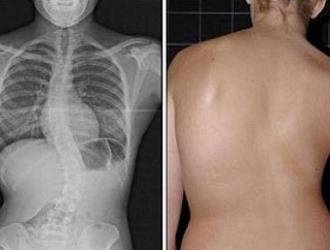

Различают следующие виды изгибов, деформаций позвоночника – кпереди (лордоз), кзади (кифоз), в ту или иную сторону (сколиоз). У человека 4 физиологических изгиба – 2 лордоза (шейный и поясничный) и два кифоза (грудной и крестцовый). Сколиозов среди физиологических изгибов нет.

Таким образом, всякое, даже едва заметное искривление позвоночника вправо или влево, безусловно, является патологией. Чаще всего сколиоз развивается в результате систематического нарушения осанки в детском и юношеском возрасте. Но это далеко не единственная причина искривлений позвоночника.

Степени сколиоза

В зависимости от угла искривления позвоночника различают 4 степени сколиоза:

- 1 степень – угол искривления от 1 до 10 градусов

- 2 степень – от 11 до 25 градусов

- 3 степень – от 26 до 50 градусов

- 4 степень – свыше 50 градусов